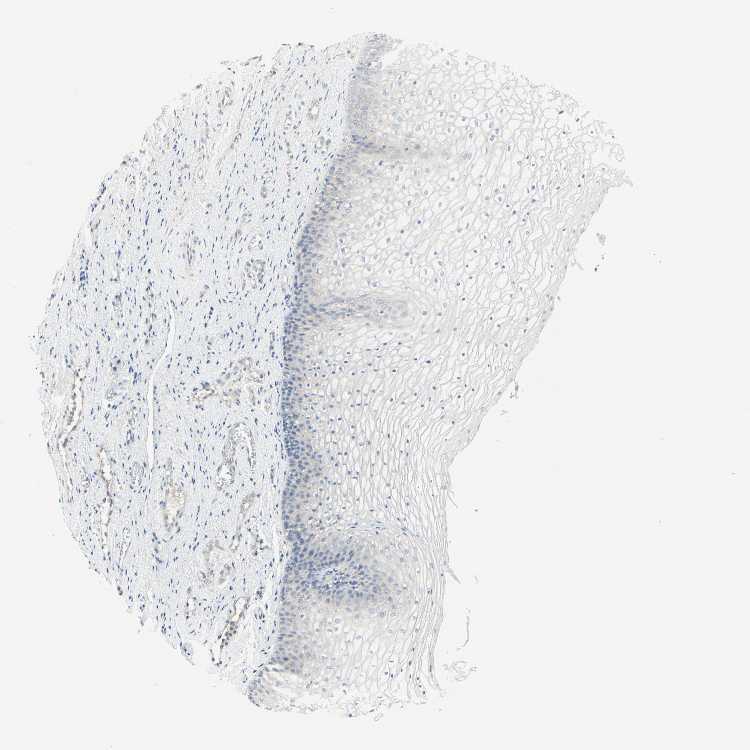

TISSUE PRIMARY DATA VAGINA Show tissue menu

VAGINA - Antibody stainingi

Antibody staining in the annotated cell types in the current human tissue is reported as not detected, low, medium, or high, based on conventional immunohistochemistry profiling in selected tissues. This score is based on the combination of the staining intensity and fraction of stained cells.

Each image is clickable and will lead to virtual microscopy that enables deeper exploration of all samples and also displays staining intensity scores, fraction scores and subcellular localization as well as patient and tissue information for each sample.

Antibody HPA010008Antibody HPA010665

Squamous epithelial cells Not detectedNot detected